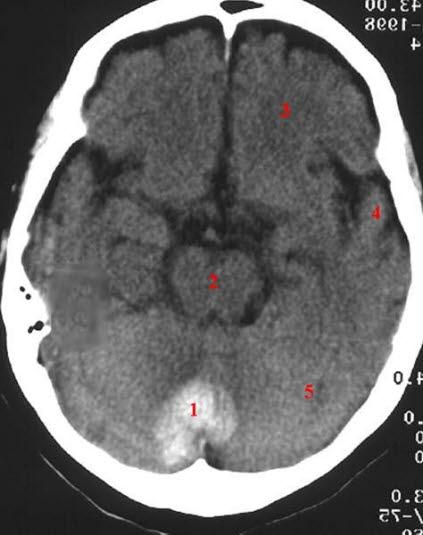

CT axialbilde uten kontrast

Blødning mellom de to cerebellar-hemisfærer

Oppstått i forbindelse med lokal trombolyse i aorta og bekkenarterier

- Blødning

- Hjernestamme

- Frontallappen

- Temporallappen

- Cerebellum